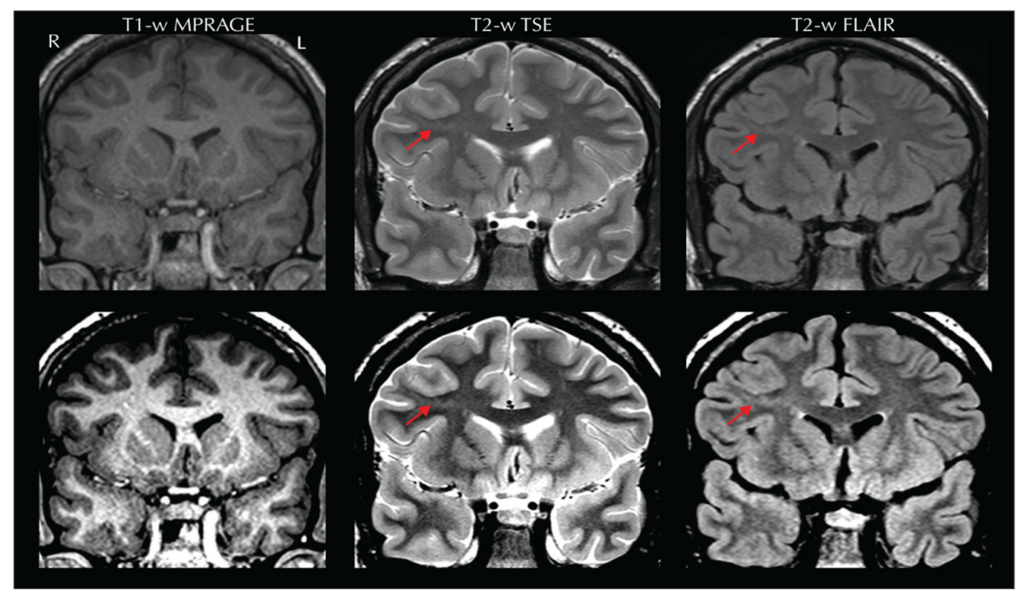

MRI features of FCD II are subtle but critical for diagnosis as Figure 4 demonstrates.

- Transmantle Sign: Funnel-shaped hyperintensity extending from the lateral ventricle to the cortex, most characteristic of FCD IIb.

- Other MRI markers:

- Abnormal cortical thickness

- Blurring of gray-white matter junction

- Signal abnormalities on T1 and T2 sequences

Subtype Examples:

- FCD IIa: Thickened cortex and hyperintensity on T2-weighted FLAIR but lacks balloon cells histologically.

- FCD IIb: Strong transmantle sign and severe cortical thickening.

Figure 5. Source: https://pubmed.ncbi.nlm.nih.gov/32763869/.